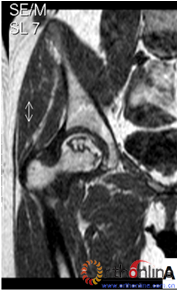

图3 各型坏死打压植骨的结果,(A)Ⅰ型(右侧)和Ⅱ型(左侧)术前MRI显示外侧柱存留;(B)术后7年随访,股骨头维持外形,关节功能好;(C)Ⅲ型(双侧)术前MRI显示外侧柱破坏;(D)术后5年,右侧股骨头维持外形,左侧塌陷

Fig 3 The results of different osteonecrotic type by impacting bone graft,(A)Type Ⅰ(right),type Ⅱ(left) MRI showed the preservation of the lateral pillar preoperatively; (B) Seven years after operation, the femoral head still maintain sphere, hip function is excellent; (C) Type Ⅲ (both side) MRI showed the involved of lateral pillar by necrosis; (D)Five years after operation, the femoral head still maintain sphere in right side, collapse occurred in left side.